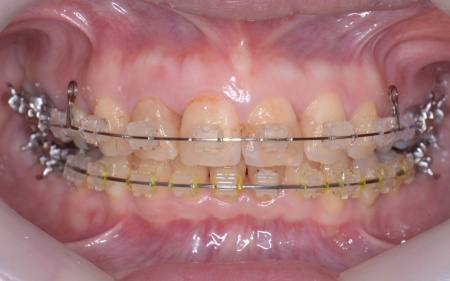

30代女性 出っ歯と開咬に対しアンカースクリューを用いたワイヤー矯正で治療した症例

まず、上顎の左右奥歯を抜き、前歯を後方に動かすためのスペースを確保します。

次にアンカースクリューを埋入し、上下の歯にワイヤー矯正装置を装着して、少しずつ歯を動かしました。

治療の結果、前歯が正しく噛み合うようになり、横顔のバランスも整いました。